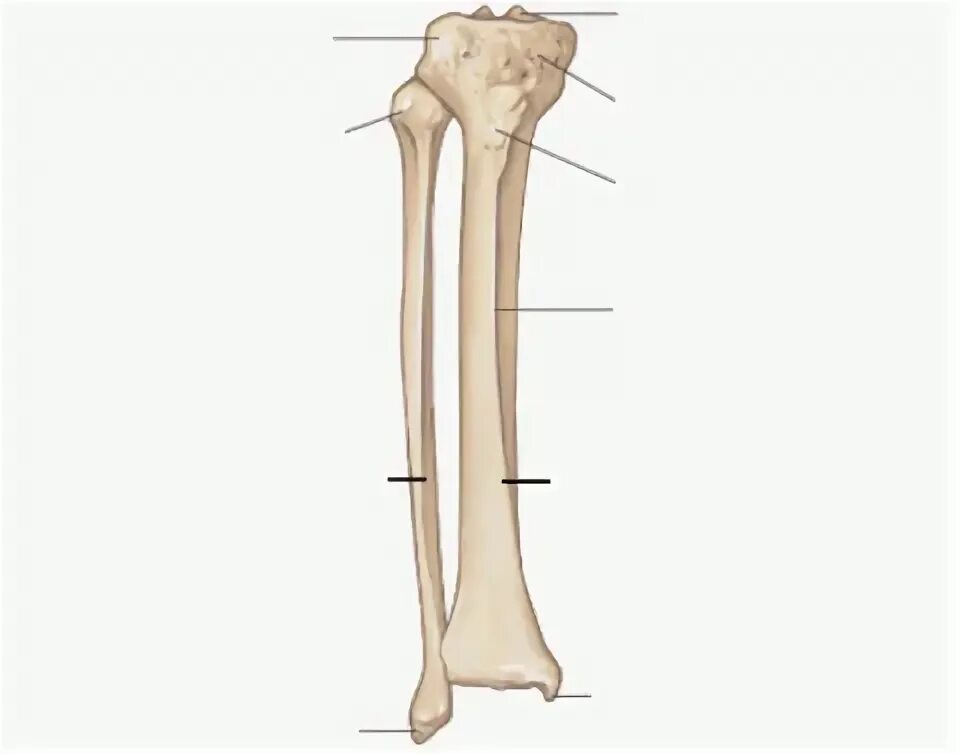

Curved tibia fibula